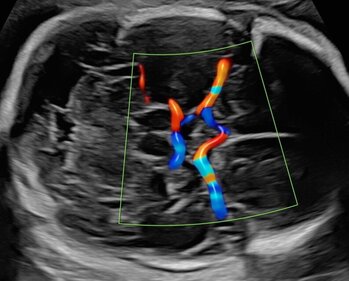

Mittels einer speziellen Feindiagnostik untersuchen wir in der Pränataldiagnostik und Schwangerenambulanz das Herz des Kindes genauer. Unter zusätzlichem Einsatz der (Farb-)Dopplertechnik können wir den Blutfluss direkt im Herzen, aber auch in den Gefäßen des Herzens messen.

Zahlreiche Herzfehler können so schon vorgeburtlich erkannt werden. Kinderkardiologinnen und Kinderkardiologen sowie Herzchirurginnen und Herzchirurgen können frühzeitig in die Beratung der Patientin eingebunden werden, sodass eine optimale Betreuung bei der Geburt gewährleistet ist. Eine frühe fetale Echokardiografie (spezielle Ultraschalluntersuchung des Herzens) kann im Rahmen der Erst-Trimester-Diagnostik zwischen der 12. und 14. SSW durchgeführt werden. Allerdings ist aufgrund der geringen Größe des Herzens die Zuverlässigkeit noch eingeschränkt. Wir empfehlen daher eine Kontrolle zwischen der 20. und 22. SSW.

Ultraschalluntersuchung der mütterlichen und kindlichen Durchblutung (Farb-Dopplersonografie)

Die Durchblutung der Nabelschnur, der kindlichen Gefäße und des Mutterkuchens wird mittels einer speziellen Ultraschalltechnik durchgeführt. Mit der sogenannten (Farb-)Dopplersonografie können wir in der Pränataldiagnostik und Schwangerenambulanz die Versorgungslage überprüfen.

Auffällige Blutflussmuster können auf eine Mangelversorgung des Ungeborenen oder Auffälligkeiten im Kreislauf der Mutter hinweisen. Zu nennen wäre hier das erhöhte Risiko für einen schwangerschaftsbedingten Bluthochdruck. Mittels der Untersuchung können solche Probleme rechtzeitig erkannt und die Patientin entsprechend am UKS überwacht werden.

Nabelschnurarterie

Gehirndurchblutung (A. cerebri media)